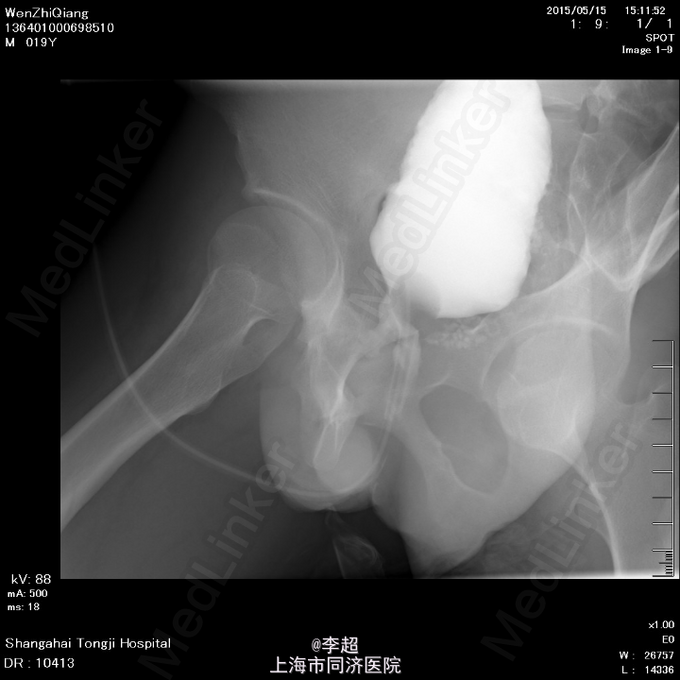

查体 辅查

患者尿道开口于阴囊下,会阴部,无法控尿,尿液自行流出 尿道造影仅显示假道,正常尿道仅存留阴茎短尿道,约5cm长

择期行耻骨下缘切除+阴囊皮瓣代尿道成形+尿道膀胱拖入术 手术过程:行会阴部倒Y形切口切口,切口包括会阴部尿道造口处,术中见阴茎部尿道存在尿道-阴茎皮肤瘘道,予切除瘘道。分离后尿道,探查见后尿道疤痕明显,并且于耻骨相连,局部粘连严重。考虑有假道存在可能,遂做耻骨上纵行切口4cm,探查膀胱发现距目前尿道口处1cm处前方存在另一内口,为盲道,盲端被变形耻骨完全遮挡。遂使用骨刀劈凿穿耻骨并切除耻骨下缘,凿通至膀胱盲道,将盲端断断显露,使用膀胱镜探查盲道,见盲端口膀胱肌肉括约功能较好,推断为真性尿道,使用左侧阴囊及大腿根部皮瓣约8cm*3cm大小,分离皮瓣下组织血管形成血管蒂,翻转皮瓣形成尿道,将皮瓣尿道近端拖入膀胱,与真性尿道膀胱黏膜处直针缝合。另将皮瓣尿道远端与阴茎部正常尿道粘膜缝合,留置F14号导尿管,假道处尿道予留置Foley14导尿管。